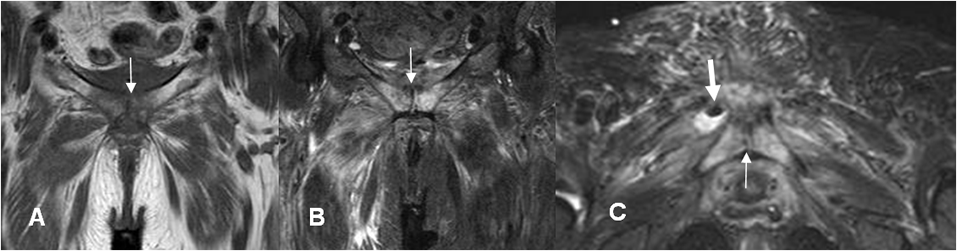

Fig 26 A. Miositis necrotizante.

A: RM coronal en T1, B: RM coronal en STIR y C: RM axial en STIR. Cambios inflamatorios en la sínfisis púbica, (Flechas delgadas) que se extiende a los músculos pectineos y obturadores a nivel bilateral y el vasto intermedio en el lado derecho. En la imagen axial se aprecia pequeña colección, con burbuja de aire en la parte superior. (Flecha gruesa).

Fig 26 B. Miositis necrotizante.